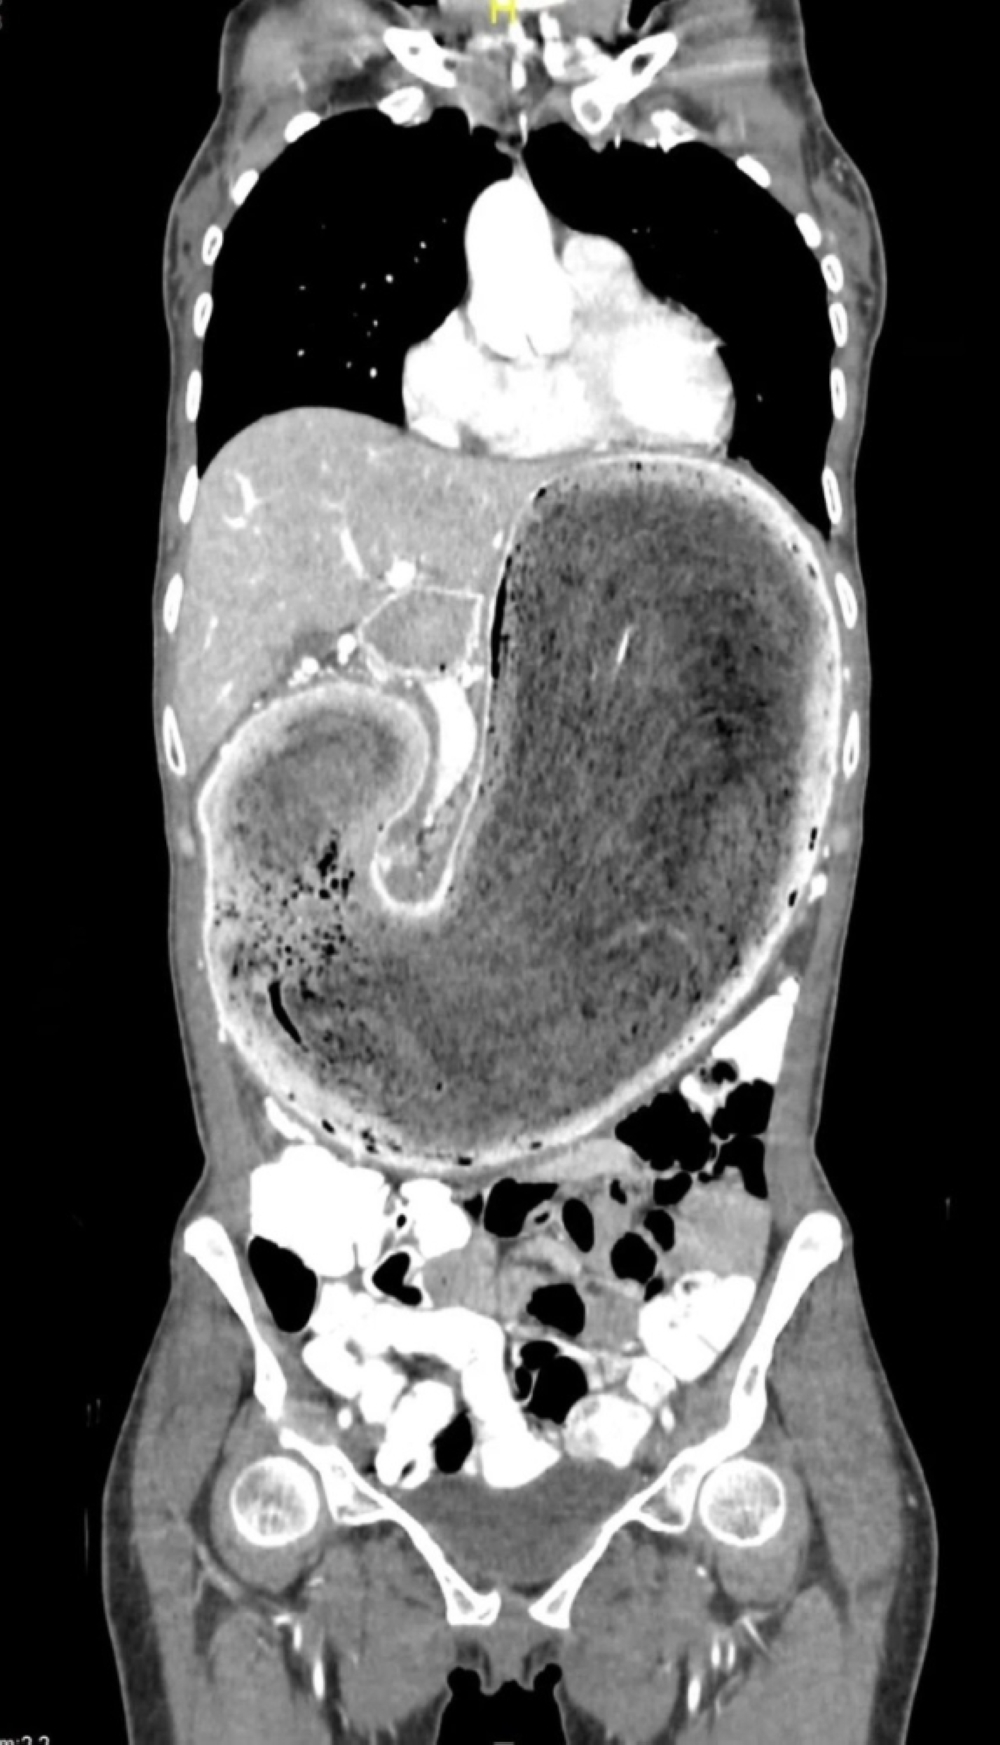

وقال تجمع مكة المكرمة الصحي العملية، إن المريضة حضرت إلى قسم الطوارئ وهي تعاني من ألم وإمساك شديد وبعد إجراء الأشعة والفحوصات اللازمة تبين وجود كتلة كبيرة من الشعر في الجهاز الهضمي والمعدة أدت إلى إغلاق المجرى الهضمي مما استدعى التدخل الجراحي، وتم نقل المريض إلى غرفة العمليات، وأجريت لها العملية، وتكللت بنجاح، وتم خروج المريضة بتحسن.

يذكر أن هذه الحالة تُعتبر من الحالات النادرة، وتسمى هوس أكل الشعر حيث يتعرض المريض إلى حالة من التوتر النفسي الشديد ينتج عنه أكل كميات كبيرة من الشعر مما يؤدي إلى حدوث مثل هذه الحالة.